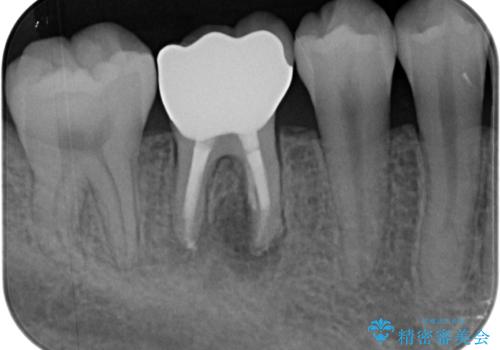

- 他院で矯正治療前後に処置を行った歯が痛むとのことで来院された患者様です。

下顎大臼歯は根管治療がされている歯が咬合時に痛みを感じ、上顎の大臼歯2歯は冷たいものがしみる状態でした。

まずはしみる上顎の歯を仮歯に置き換え、その後下顎の根管治療を行った上で、異常が認められなければオールセラミッククラウンにて補綴治療を行うこととしました。

根管治療を行った歯の周辺にある病変は数ヶ月後にレントゲン写真を撮って確認する必要があるため、今後経過観察を行っていく予定です。